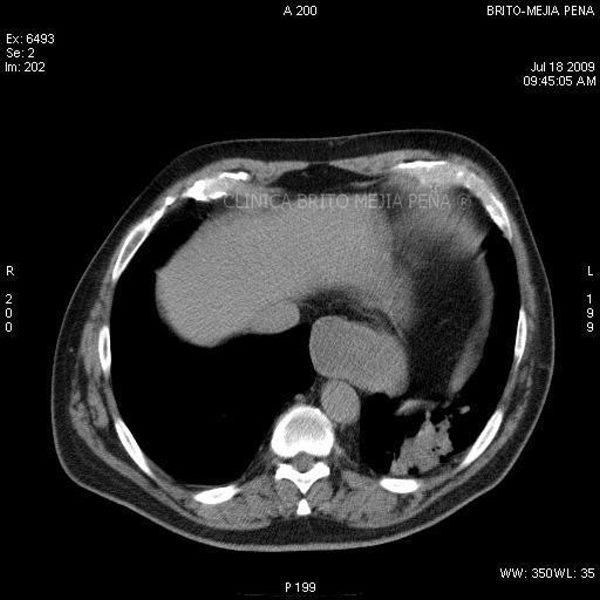

Trombosis arteria pulmonar axial